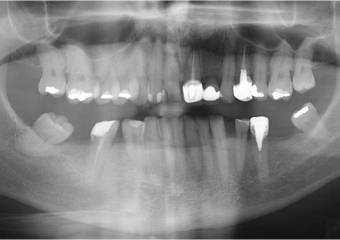

Raio X das próteses fixas em porcelana